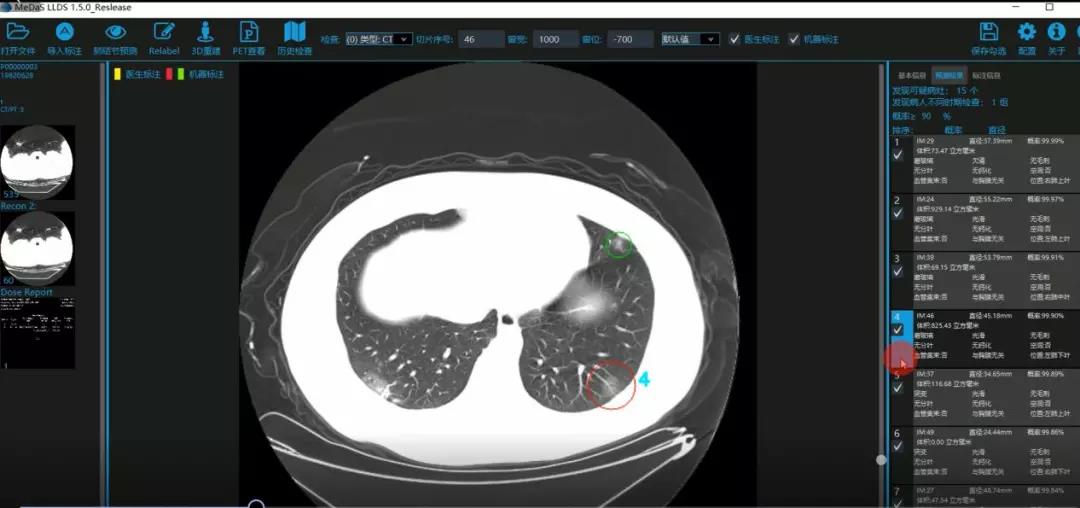

医护人员的好帮手:基于深度学习的新冠肺炎早期检测筛查系统

西电beat365唯一官方网站智能软件与系统新技术研究所副教授张亮的爱人是西安交通大学第二附属医院抗疫一线的影像科医生,疫情发生以来,他们讨论最多的就是新型冠状病毒感染者的早期诊断问题。作为一名医护家属,身为高校科研工作者,张亮深知快速准确地诊断新冠肺炎早期患者对控制和防治疫情的重要性和挑战性。他与团队成员主动出击,通过远程网络会议,在前期医学影像处理的研究基础上加速科研攻关,反复讨论方案,屡次设计模型,与上海宽带技术及应用工程研究中心、上海交通大学医学院附属瑞金医院等合作单位的人员多次标注整理患者肺部CT影像数据到深夜。与此同时,他们依托上海瑞金医院、西安交通大学第二附属医院等的新冠肺炎疑似、确诊患者肺部CT影像,通过综合分析新冠肺炎患者的肺部CT影像特点(磨玻璃、体积大小、位置等特征),张亮团队加快技术攻关,设计开发了基于深度学习的新型冠状病毒的早期检测筛查模型系统。

对应新冠肺炎CT病灶检测效果

令人欣喜的是,通过对实际门诊数据排查测试,该模型可以减轻医护人员近80%的工作量,新冠肺炎患者的检测召回率超过95%。目前,模型系统正在进行最后的调试工作,很快投入到“战疫”一线,缓解医护人员紧缺、确诊检测工作耗时较长等问题,减少医护人员的工作时间和劳动强度,提高工作效率。